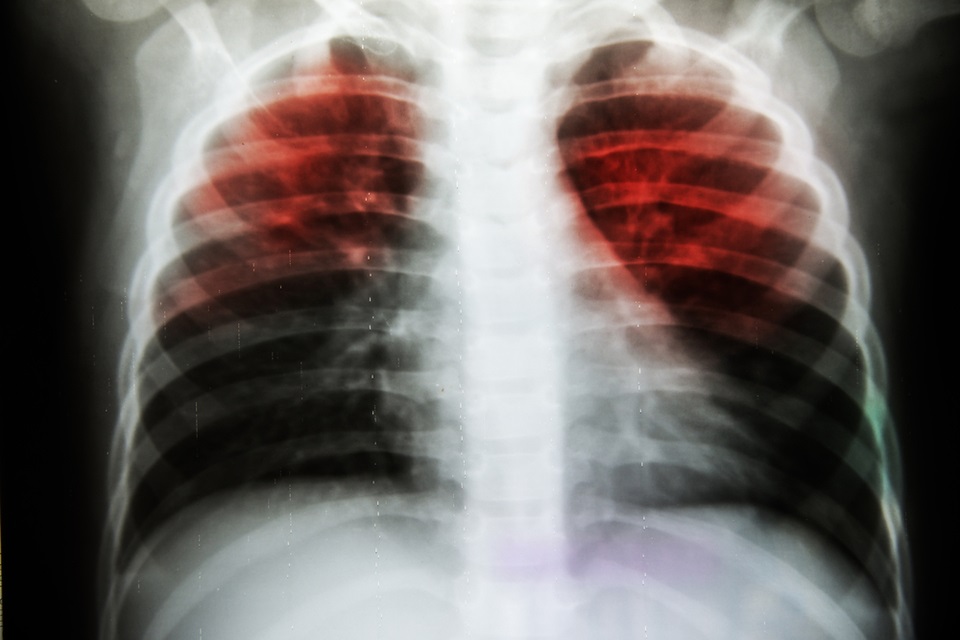

Tuberculosis is still a significant healthcare problem around the world and is the 10th most common cause of death worldwide, while almost half of TB patients also report suffering from depression as well.